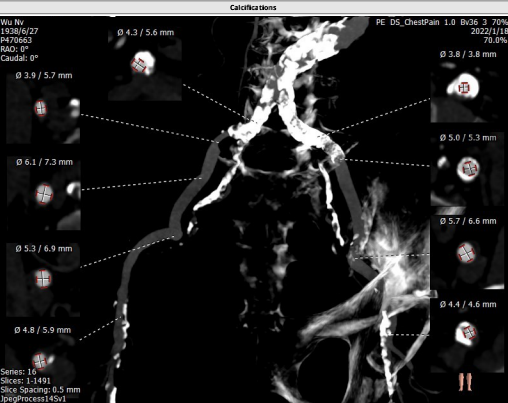

主动脉CTA:

主入路CTA:

吴伟、李荣教授团队术前总结了该病例特点:此例患者为三叶瓣重度主动脉瓣狭窄病人,瓣环72.8mm,LVOT24.0 mm,瓦式窦均径30mm,STJ 28.3mm,升主动脉41.2mm,左冠高度8.3mm,右冠高度14.4mm,下肢入路右侧血管最小径4.8mm,左侧最小径3.8mm,通过入路超声造影,显示右侧入路血管极其狭窄且重度钙化,特别是主动脉弓部钙化较重,但主动脉根部解剖形态较好,瓣叶钙化较重,考虑到球囊预扩后瓣叶可推开,由于左冠开口较低,在选择球囊型号和输送系统型号上是本次手术的关键点。